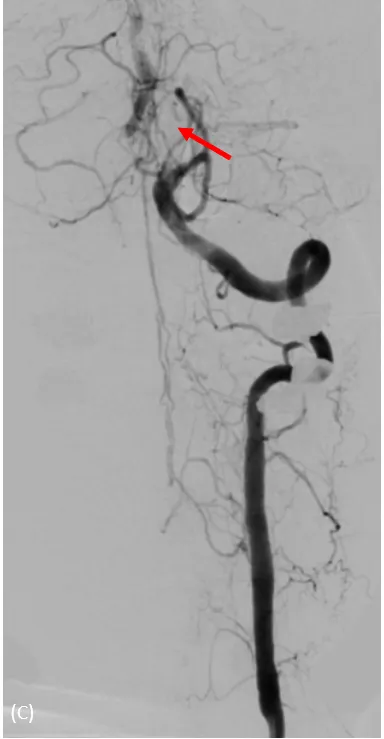

動脈穿刺血管攝影,兩側椎動脈完全阻塞,經由細小分枝供應腦幹的血流。大里仁愛醫院提供